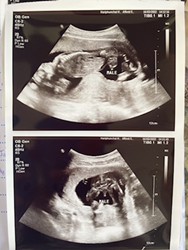

พอดีเราไปอัลตร้าซาวด์มาหมอบอกน่าจะผู้หญิง 50% ถ้าเป็นแบบนี้แม่ๆท่านไหนมีประสบการณ์บ้างคะและแบบนี้เป็นผู้หญิงหรือเป็นผู้ชายคะ

เหมือนผู้หญิงเลยค่ะ

เหมือนผู้หญิงนะค่ะ

เราว่าผู้หญิงค่ะ

น่าจะผู้หญิงนะคะ